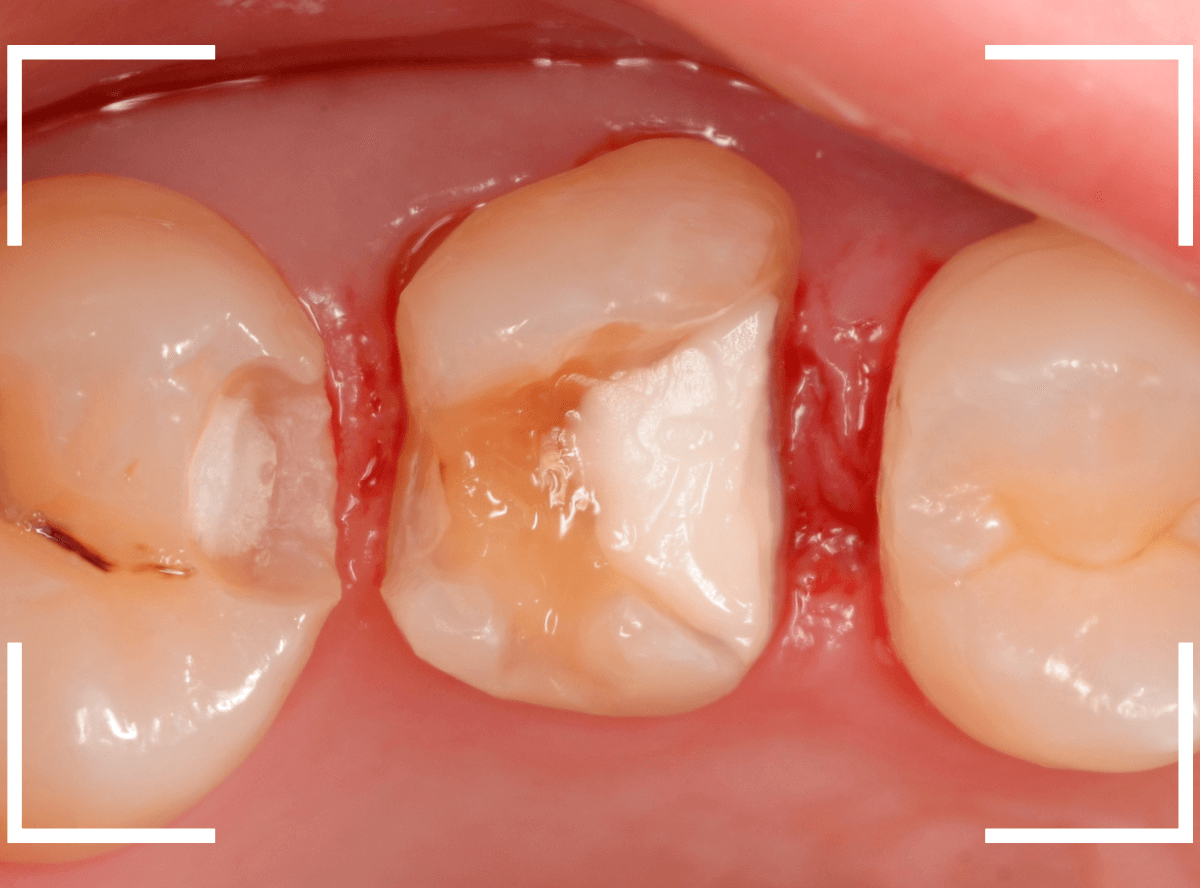

虫歯の治療を開始します。

隣の歯とのすき間を中心に広い虫歯になっていました。

虫歯治療後、特に症状もなく経過観察できましたので、つめものを作る治療に入ります。

セラミック治療をご希望されましたので、

小臼歯をE-MAX・インレー、

大臼歯をジルコニア・インレーで処置することになりました。